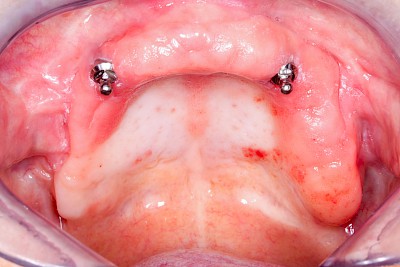

Schlechter Halt & schlechte Passung

Immer wieder kommt es vor, dass Zahnprothesen schlecht passen und/oder schlecht halten. Eine schlechte Prothesenpassung zeigt sich daran, dass die Prothese stark "schaukelt", wenn man auf die Zahnreihen drückt. In erster Linie ist dies auf den Knochenschwund, die sogenannte Atrophie, zurückzuführen. Knochenschwund ist individuell sehr unterschiedlich ausgeprägt. Genetische Veranlagung aber auch intensives Tragen der Zahnprothese sowie ständiges Knirschen und Pressen können Einflussfaktoren sein.

Ein übermäßiger Bedarf an Haftmitteln wie zum Beispiel Haftcreme, lässt ebenfalls auf eine schlechte Passung schließen. Halten Prothesen auch mit normaler Menge Haftcreme nicht, sollte ein Zahnarzt gerufen werden.

Bei manchen Prothesen verschlechtert sich der Halt, weil die Haltewirkung der Verbindung zwischen der Prothese und den Restzähnen oder Implantaten nachlässt. Nicht selten sind auch einzelne Verbindungs- bzw. Verankerungselemente einfach "verloren" gegangen (verschluckt, ausgespuckt und ganz selten aspiriert!). Manchmal stecken die Kronen, die die Prothese mit den Restzähnen verbinden, in der herausnehmbaren Prothese. In Ausnahmefällen sind die Ankerzähne oder Implantate selbst nicht mehr im Knochen fest verankert und gehen mit der Prothese insgesamt raus. In allen diesen Fällen sollte der Zahnarzt gerufen werden.